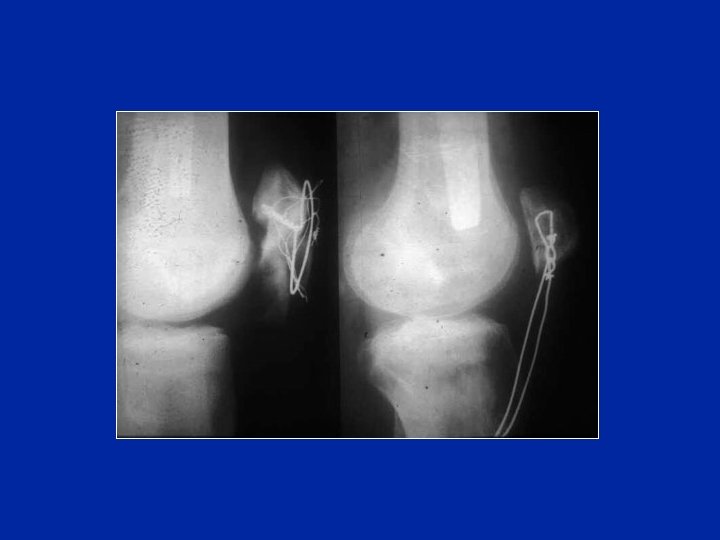

Cerclage de mauvaise qualité

Repris par un haubannage de mauvaise qualité !

Débricolage aboutissant à une pseudarthrose

Traitement par avivement de la pseudarthrose et mise en compression par un nouveau hauban

Aspect 12 ans plus tard Bonne flexion, bonne fonction, remaniements de la rotule et de l’interligne